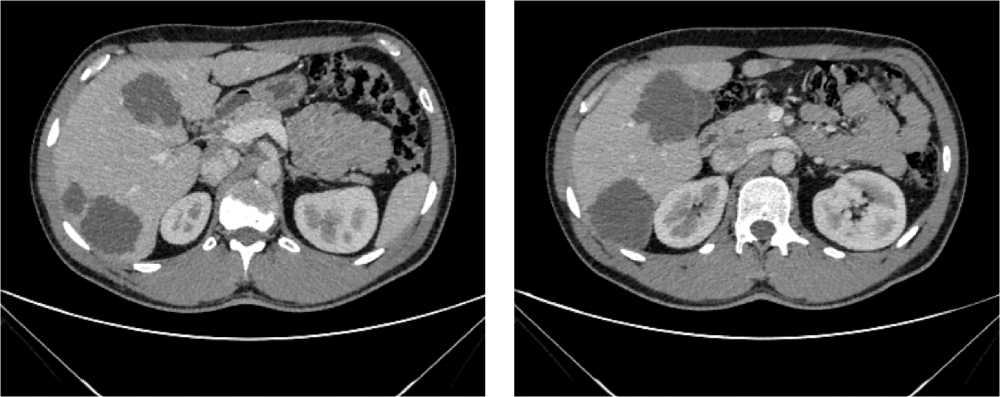

По результатам КТ органов брюшной полости (ОБП) от 08.2023, поддиафрагмально слева сохраняется инфильтрат 79 × 46 мм, распространяется на большую кривизну желудка, брюшину, диафрагму слева и по левому фланку брюшной полости. Желудок деформирован, стенки утолщены. Парагастральная и внутрибрюшинная клетчатка слева инфильтрирована. По брюшине сохраняются образования. Эффект лечения оценен как частичный регресс (рис. 6).

Рис. 6. Частичный регресс, по данным компьютерной томографии органов брюшной полости, на фоне иммунотерапии пембролизумабом у пациента 63 лет с диагнозом метастатический колоректальный рак с признаками микросателлитной нестабильности (август 2023 г.)

Fig. 6. Partial regression according to abdominal CT scan during immunotherapy with pembrolizumab in a 63-year-old patient with metastatic MSI-H colorectal cancer (August 2023)

С учетом достигнутого частичного ответа на фоне ИТ, отсутствия, по данным КТ, абсолютных признаков нерезектабельности рецидивного образования левой поддиафрагмальной области, пациенту выполнена комбинированная операция в ноябре 2023 г. в следующем объеме: удаление внеорганного рецидива опухоли с корпорокаудальной резекцией поджелудочной железы, sleeve-резекцией желудка, резекцией левого купола диафрагмы и восстановлением непрерывности толстой кишки.

По результатам гистологического исследования выявлен полный патоморфологический регресс I степени по Mandard. В краях резекции признаков опухолевого поражения не обнаружены. ЛУ также без признаков опухолевого поражения.

В настоящее время пациент находится под динамическим наблюдением без признаков прогрессирования заболевания (время без прогрессирования составило 22+ мес.).